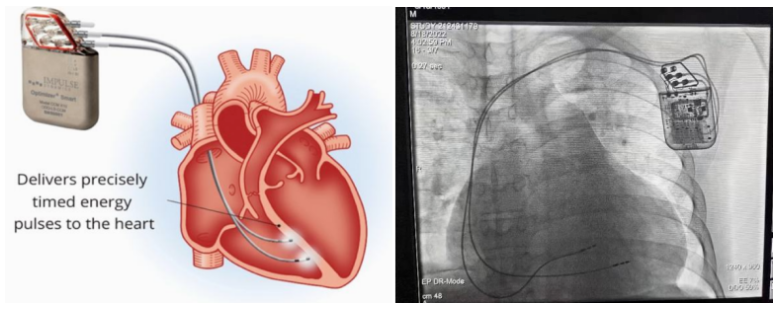

①植入式心臟復(fù)律除顫器

Implantable Cardioverter Defibrillator,ICD

植入式心臟復(fù)律除顫器是一種具有除顫功能的高級起搏器,是一種體積小、能植入患者胸部皮下組織的醫(yī)療設(shè)備。慢性心衰患者易發(fā)生室性心動(dòng)過速或心室顫動(dòng),導(dǎo)致心源性猝死(SCD)。ICD 則能在幾秒內(nèi)自動(dòng)識別并治療快速室性心律失常,通過低能量心臟轉(zhuǎn)復(fù)和高能量除顫等功能,顯著降低惡性室性心律失常引起的猝死風(fēng)險(xiǎn)??杉皶r(shí)自動(dòng)為患者轉(zhuǎn)復(fù)心律,通俗地說就是裝在體內(nèi)的自動(dòng)除顫儀。

國內(nèi)研發(fā)企業(yè):無雙醫(yī)療、邁瑞、魚躍、久心、微創(chuàng)、維偉思、麥邦等